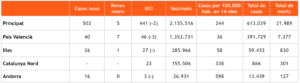

Sanitat

Report diari sobre el coronavirus: El País Valencià, el territori amb més bons indicadors del sud d’Europa

Report diari sobre el coronavirus: El País Valencià, el territori amb més bons indicadors del sud d’Europa

Report diari sobre el coronavirus: El País Valencià, el territori amb més bons indicadors del sud d’Europa